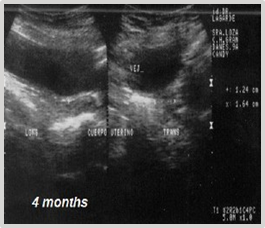

The cryosurgical option was suggested, but the owner declined. Four months later, during a follow-up ultrasound examination, an increase in the mass to 2.90 cm x 2.50 cm was confirmed (Figure 2). Faced with this situation, the owner agreed to the intervention.

Figure 2 Ultrasonographic diagnosis of bladder four months later: Increased mass measuring 2.90 cm x 2.50 cm.